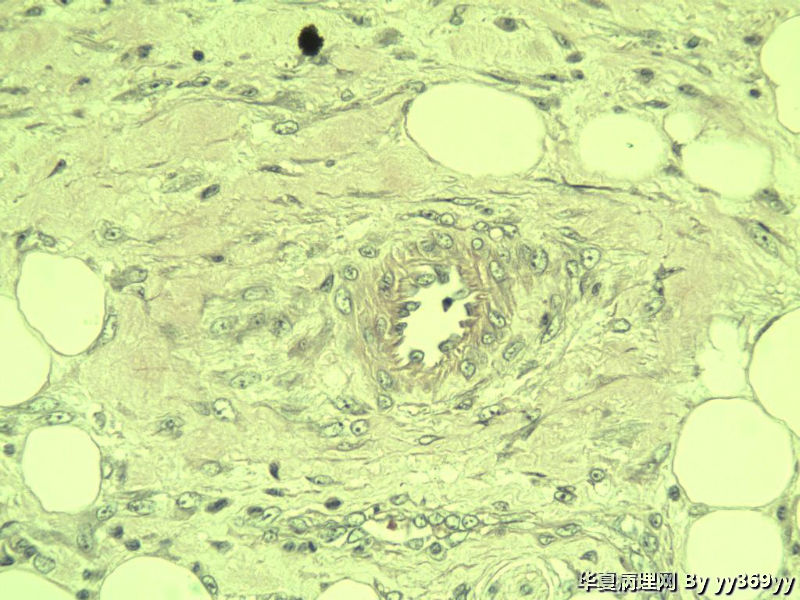

小肠肿瘤图4

上面几张图是淋巴结

第一次发的图片有低倍的吗,与长肠壁关系呢?第二次发的是神经节细胞

这些都是增生的神经节细胞,在溃疡周围的正常粘膜里找找看有无肉芽肿

神经节细胞

补取了几块 肌层纵行和横行平滑肌之间很多这种细胞 是什么??